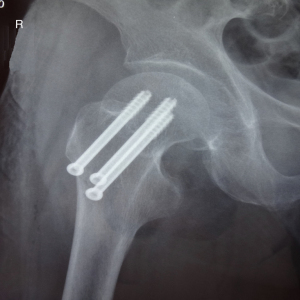

The patient was a 63-year-old male worker, previously fit and well, who fell and hurt himself by accident. He felt severe pain in his left hip and was sent to Affiliated Hospital of Shandong University of Traditional Chinese Medicine immediately. We found external rotation deformity of his left limb and performed an X-ray examination. Unfortunately, we found a left femoral neck fracture (Garden Index III) (Figure 2). Due to the significant displacement, the patient was treated surgically with closed reduction and percutaneous internal fixation using three parallel cannulated screws placed in an inverted triangle configuration. The three guide pins were inserted (Figure 3) into the three guide pin insertion points (C1, C2, and C3) that had been located with our localization method (Figure 4). Then three parallel cannulated screws were implanted to fix the fracture (Figure 5). Postoperative follow-up was performed periodically over 12 months to evaluate the hip function and observe complications. Overall, we achieved a satisfactory therapeutic outcome without complications (Figure 6).